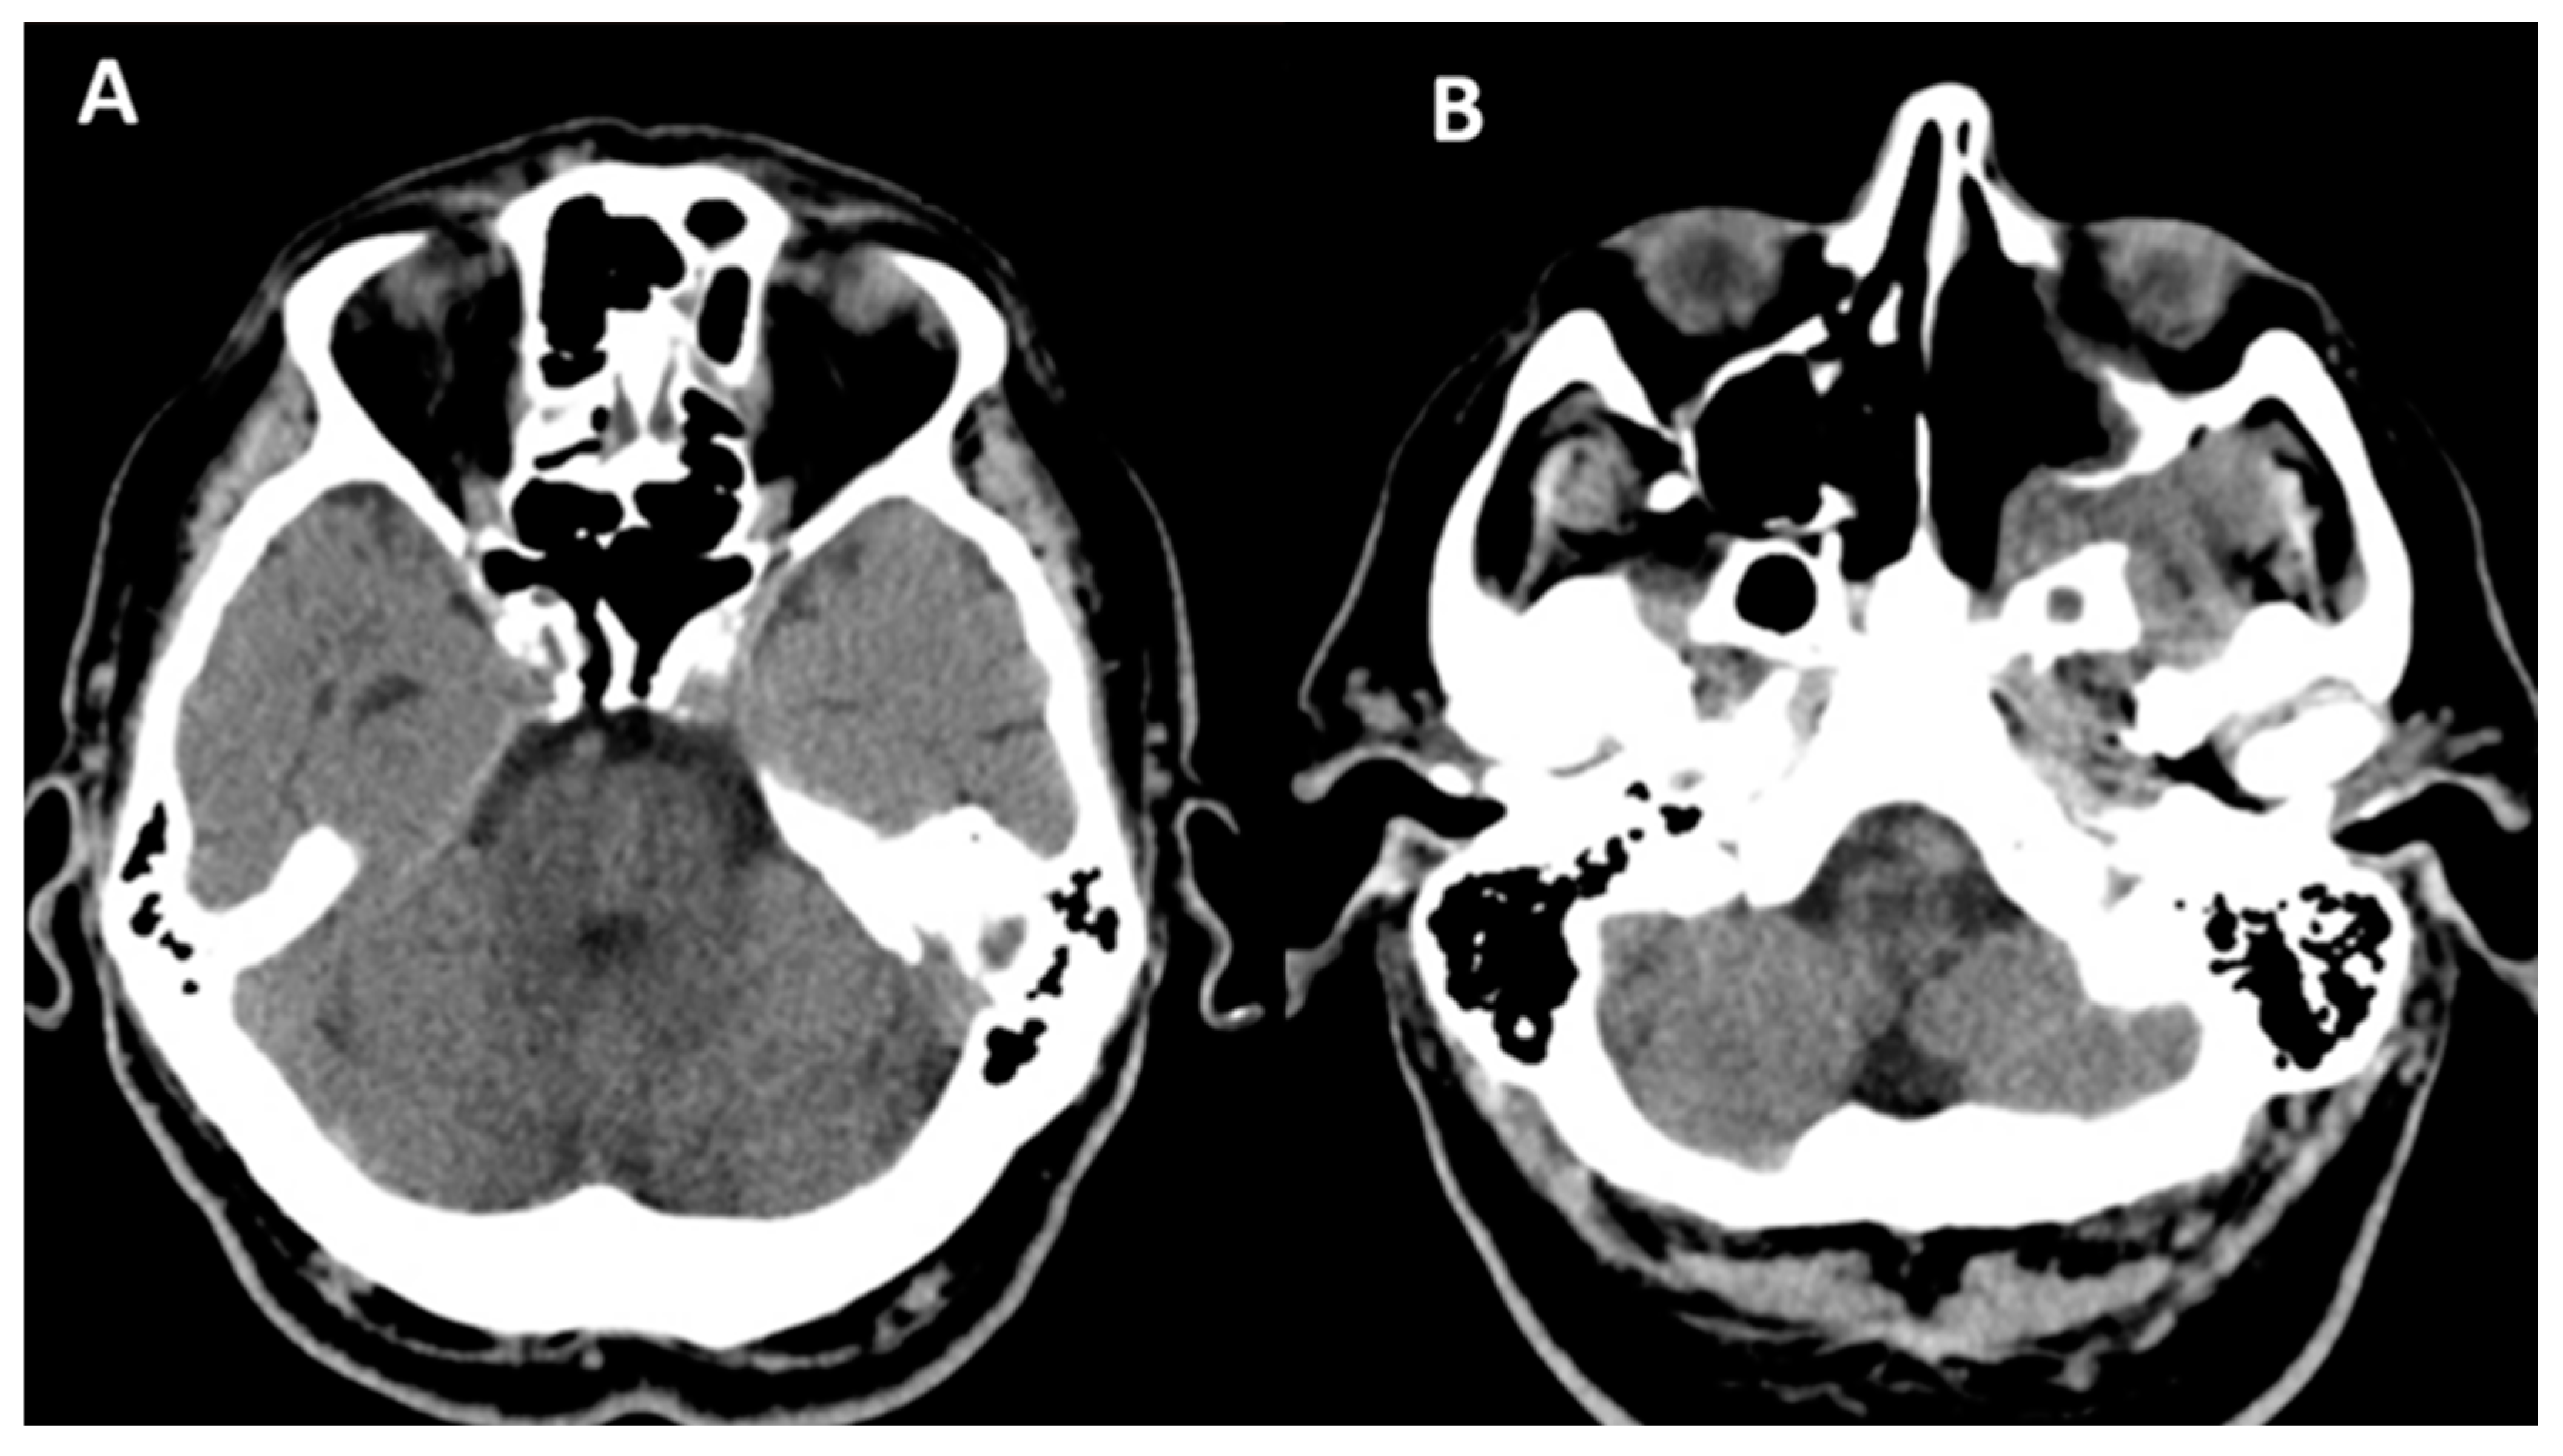

Subsequently, on 30 August 2022, he developed edema in the upper and lower eyelids, diffuse facial edema with Celsian signs, and associated centrofacial vascular necrosis at the level of the nasal pyramid with right orbital extension and the involvement of the right maxillary sinus, accompanied by headache, leading to admission to the Ear Nose Throat (ENT) department, Figure 2. A macroscopic anatomopathological examination revealed multiple necrotic fragments and a microscopic examination showed multiple histological sections represented by necrotic-inflammatory material, with numerous bacterial colonies and fungal filaments, and some branching at a 90-degree angle, consistent with mucormycosis, Figure 3. Cranial CT showed massive destructive infectious processes involving the maxillary sinuses, posterior ethmoid cells, and orbits with involvement of the right eye globes, possibly of mixed fungal and bacterial etiology, Figure 4. Surgical treatment was instituted by performing a total necrectomy of the centrofacial necrotic focus along with antibiotics (amoxicillin-sulbactam, cefoperazone) for 10 days and antifungal therapy with posaconazole (for 9 weeks) due to myelosuppression. Amphotericin B and isavuconazole were not available at that time in the hospital. Postoperative recovery was satisfactory, and subsequently, he was transferred to the hematology service for further specialized treatment.

Figure 4. Cranial CT (scale bar equals 1.25 mm). (A,B) The image of the coronal computed tomography shows thickening of the mucosa and homogeneously walled-off collections with air inclusions, localized in the left sphenoidal sinus, bilateral frontal maxillary sinuses, and ethmoidal cells, post-necrotic bone structure changes with the interruption of the bone cortex, and multiple osteolytic lesions in the bilateral fronto–ethmoido–maxillary regions, as well as in the nasal septum and nasal bones. (C,D) Right eyeball with reduced dimensions and altered structure with a shrunken appearance.